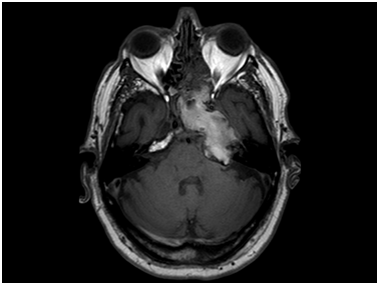

Evolution:There were no postoperative incidences. MR from 7days after surgery (Figure 4) showed a decrease of the lesion size compared with the preoperative image observing a more heterogeneous content in T1 signal and air bubbles in relation to the recent surgery. During the 2-year follow-up the patient was asymptomatic and stable, requiring no additional endoscopic neurosurgical treatment.

Figure 4 Postoperative axialT2-weighted MR image showing a decrease of the lesion size compared with the preoperative image observing a more heterogeneous content in T1 signal and air bubbles in relation with the recent surgery.